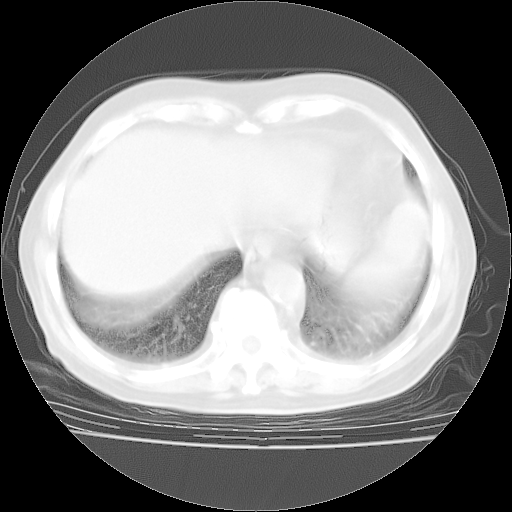

4月28日肺部CT——再次出现类似去年5月9日——透光度降低,“间质性”改变。

4月28日肺部CT——再次出现类似去年5月9日——磨玻璃样、间有“粟粒样”改变。

个人阅读4.14日肺部CT平扫:纵隔窗无异常,但肺窗示:双下肺内、后基底段有片絮状侵润影,部位以后基底段为著,以间质改变为主,呈急性肺泡炎征像,和首次住院影像学有相似之处。仅是个人读片,明日请相关专家再读片哈。其它建议同上。

1、108#的是4月14日的胸部CT(发此贴时还没看着28日的CT)。14日的胸部CT其实已经出现改变(如108#所述),个人认为28日的胸部CT除纵膈窗疑似有双侧胸膜增厚或少量胸积液(可行胸部B超明确)外,与4月14日对照病变有所加重;2、已经给予“异烟肼、利福平、乙胺丁醇”抗痨治疗?如果是,甲强龙80mg可缓慢减量;如果环磷酰胺已停用,暂不使用;3、中性粒细胞92%,明显升高,目前体温情况?注意合并细菌感染可能,使用左氧氟沙星情况下,是否联用B-内酰胺类抗菌药物?另外是查免疫全套非风湿全套。

今请临免主任会诊后认为:4月14日胸部CT已有双下肺间质性改变。患者病情复发多系激素减量过快不正规所致。目前甲强龙80mg/日,一周后酌情开始减量,不易过快。环磷酰胺若已停用,暂不使用。他同意目前抗菌药物使用,但应考虑是否加用B-内酰胺类抗菌药物(中性细胞明显增高);2、结核复发目前依据不足;3、若免疫全套各项指标正常,考虑多系特发性肺间质炎可能大。4、加强支持,并注意保护胃黏膜。

今上午去请教了临免、呼吸主任:1、介绍病史和阅读系列胸部CT一致认为:患者肺结核不考虑,仍为肺间质纤维化,目前处于急性肺泡炎阶段。2、若仍发热,可将甲强龙增至:80mg Bid静滴,同时鉴于中性增高,合并细菌感染可能,继续左氧氟沙星治疗,再联用B-内酰胺抗菌药物,如头孢哌酮--舒巴坦;3、停用抗痨药;4、目前甲强龙每日剂量160mg ,体温正常后再酌情减量;目前暂不用免疫抑制剂;4、不建议使用免疫增强剂等;5、加强支持治疗,鼓励患者进食;5、注意随访肝、肾功及血常规情况;6、因患者目前激素用量较大,加用胃黏膜保护剂,防止消化道出血可能。